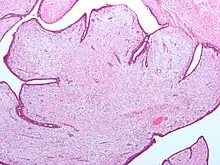

| Fibroepithelial neoplasm (Phyllodes tumor). | |

A fibroepithelial neoplasm (or tumor) is a biphasic tumor. They consist of epithelial tissue, and stromal or mesenchymal tissue. They may be benign or malignant.[1]